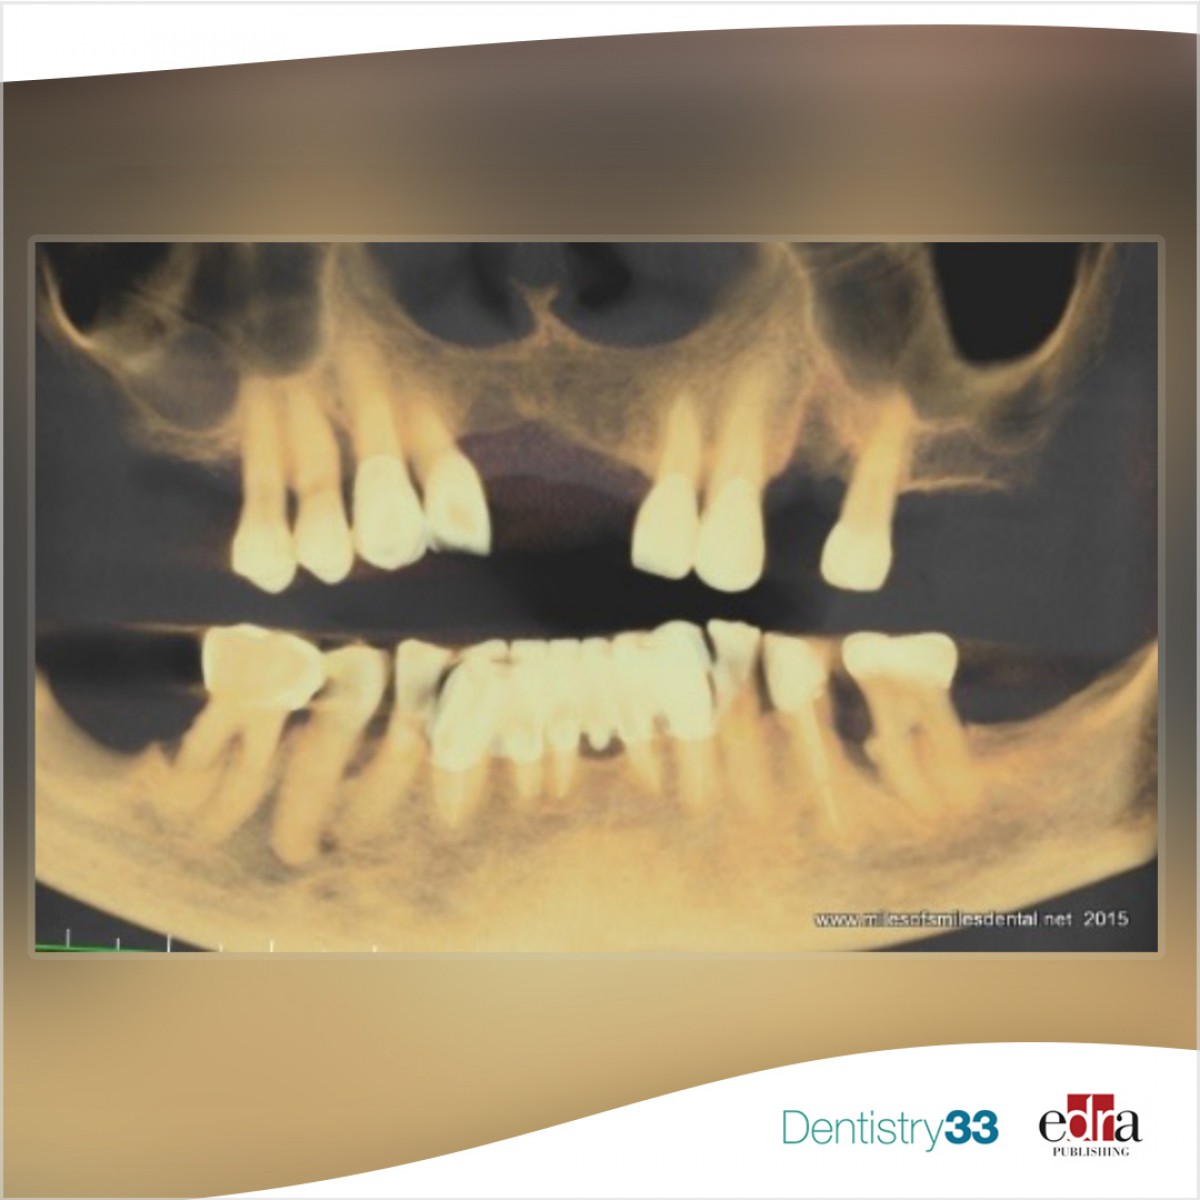

A 59-year-old male presented partially edentulous with severe collapse in the vertical dimension of occlusion. Most teeth were periodontally involved or fractured at the gingival level. The periodontally involved teeth had mobility type II with moderate to advanced bone loss and gingival recession (Figure 1, above).

Only three mandibular teeth were present with no teeth remaining in the mandibular left quadrant and moderate to advanced vertical bone loss (Figure 2). A cone beam CT scan was obtained and reviewed to assess bone levels, anatomy as well as critical anatomical structures in the areas of planned implant placement (Figure 3).